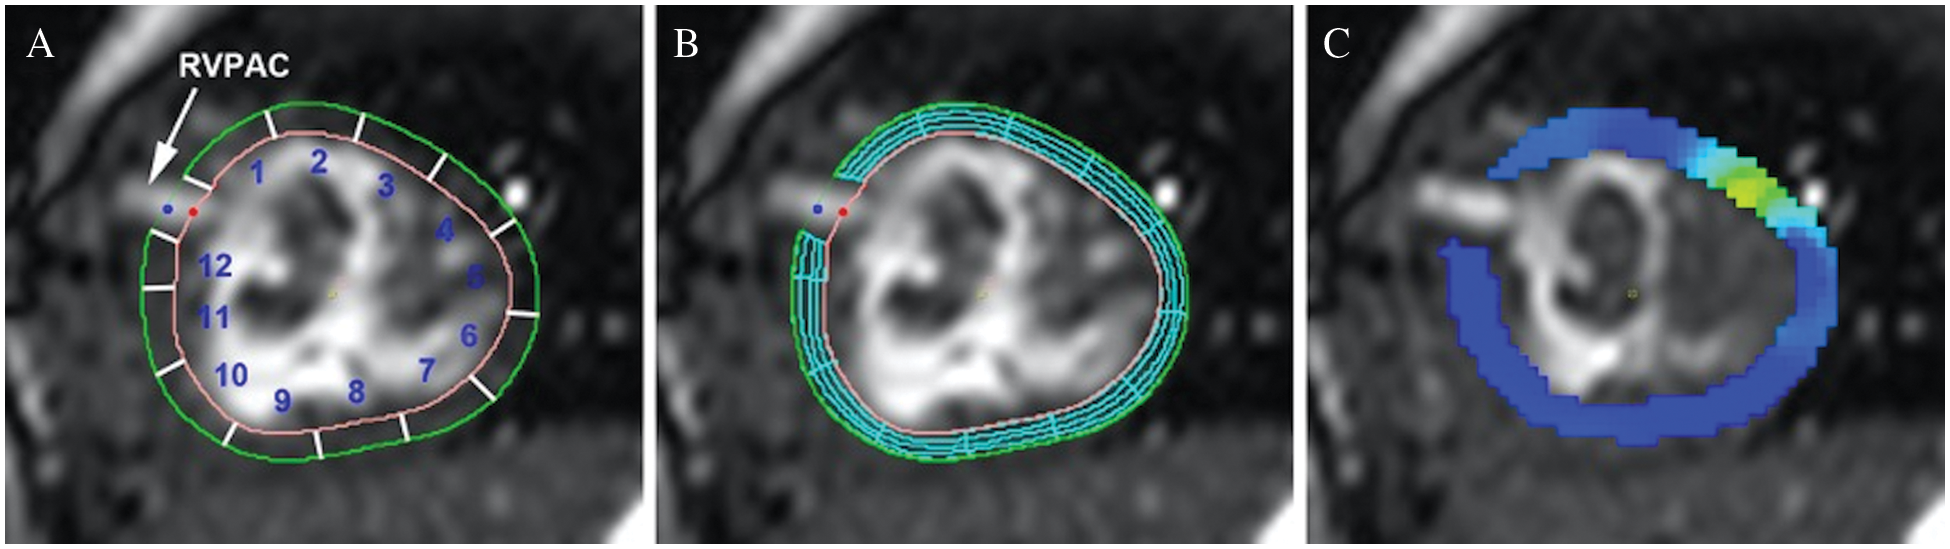

Peak regional radial and circumferential strain were assessed using feature tracking analysis (CVI42, Calgary, Canada) on steady-state free precession ventricular images in the ventricular short-axis plane. Open contours of the endocardium and epicardium were manually drawn to exclude the conduit insertion site and adjusted as needed to ensure accurate tracking. The contour was automatically divided into 12 equal segments. Segments were labeled in a clockwise fashion with segment 1 directly anterior and superior to the conduit insertion site and segment 12 posterior and inferior to the conduit (Fig. 2A). For CMR studies performed after RVPAC takedown, a closed contour technique was used with reference points at the presumed site of RVPAC insertion to keep the labeled segments consistent. Peak segmental circumferential and radial strain measurements were calculated (Figs. 2B and 2C). Circumferential strain represents fiber shortening and has a negative value. Therefore, more negative circumferential strain indicates greater shortening and is characterized as “better” (vs. “worse”) circumferential strain throughout the article. More positive radial strain is consistent with greater myocardial thickening and is referred to as “better” (vs. “worse”) radial strain.

Figure 2: Myocardial contour and feature tracking techniques

Panel A: Open contours of endocardium and epicardium with segments labeled in a clockwise fashion. Segments 1, 2, 11, and 12 represent segments of interest for comparison between conduit types. Panel B: Feature tracking analysis with mesh overlay. Panel C: Peak circumferential strain (dark blue represents better strain).

The primary outcomes were peak radial and circumferential strain of the four segments most proximal to the RVPAC (regions 1, 2, 11, and 12 in Fig. 2A). Additional secondary outcomes included the presence of LGE at the RVPAC site and transplant-free survival. For survival analysis, follow-up was measured from the date of Stage I operation to death, transplant, or the last known follow-up date.